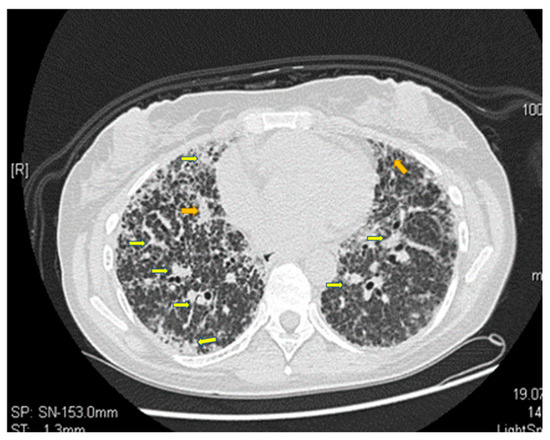

5. Evidence-Based Assessment of a Patient with RA and LAM